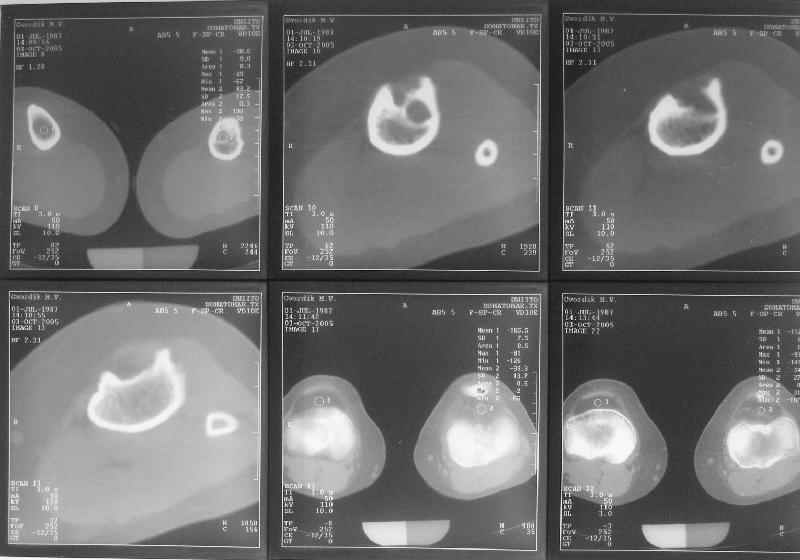

Жалобы у нее на появившиеся боли в колене при нагрузках. Признаков воспаления не было и нет, опухолевого роста также. Природа дефекта в области бугристости не очень понятна. Дополнительно сделали КТ и боковой снимок в максимальном разгибании - все в приложении.

По-поводу деформации - Вы имеете дело с епи-метафизарной деформацией, скорее всего по причине преждевременного частичного закратия проксимальной зоныы роста большеберцовой кости.

За точку отсчёта при планировании коррекции надо взять латеральный снимок в максимальном стрессе на разгибание. Остеотомию необходимо произвести тот час дистальнее места прикрепления собственной связки надколенника.(очень важно)

На сегодня заключение рентгенолога - монолокальная монооссальная фиброзная дисплазия.